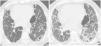

High-resolution computed tomography (HRCT) is the imaging method of choice for the evaluation and diagnosis of interstitial lung diseases because it confirms the presence of lung disease and establishes the correct diagnosis for associated complications. Nevertheless, the definitive diagnosis of these entities requires the imaging findings to be interpreted together with their clinical manifestations and histological confirmation. In this group of diseases, HRCT findings play a fundamental role, being especially important for avoiding unnecessary biopsies. For these reasons, clinicians need to be familiar with the basic radiologic patterns associated with this group of lung diseases: septal, reticular, nodular, ground-glass, cystic, and consolidations. This chapter describes the features of these patterns and ways that they can present, and it reviews some of the most common interstitial lung diseases, emphasizing the predominant radiologic patterns in each of them.

La tomografía computarizada de alta resolución (TCAR) es el método de imagen de elección en la evaluación y el diagnóstico de las EPID, ya que confirma la presencia de enfermedad pulmonar y establece el correcto diagnóstico de las complicaciones asociadas. No obstante, el diagnóstico definitivo de estas enfermedades requiere la concordancia con las manifestaciones clínicas y la comprobación anatomopatológica. Las imágenes radiológicas obtenidas por la TCAR en este grupo de enfermedades tienen un papel fundamental, de especial importancia para evitar la realización de biopsias innecesarias. Por estas razones, el médico clínico debe familiarizarse con los patrones radiológicos básicos asociados a este grupo de enfermedades pulmonares: septal, reticular, nodular, en «vidrio deslustrado», quístico y de condensación. En este capítulo se describen las características y la forma de presentación de estos patrones, y se revisan algunas de las EPID más frecuentes, haciendo hincapié en los patrones radiológicos predominantes en ellas.